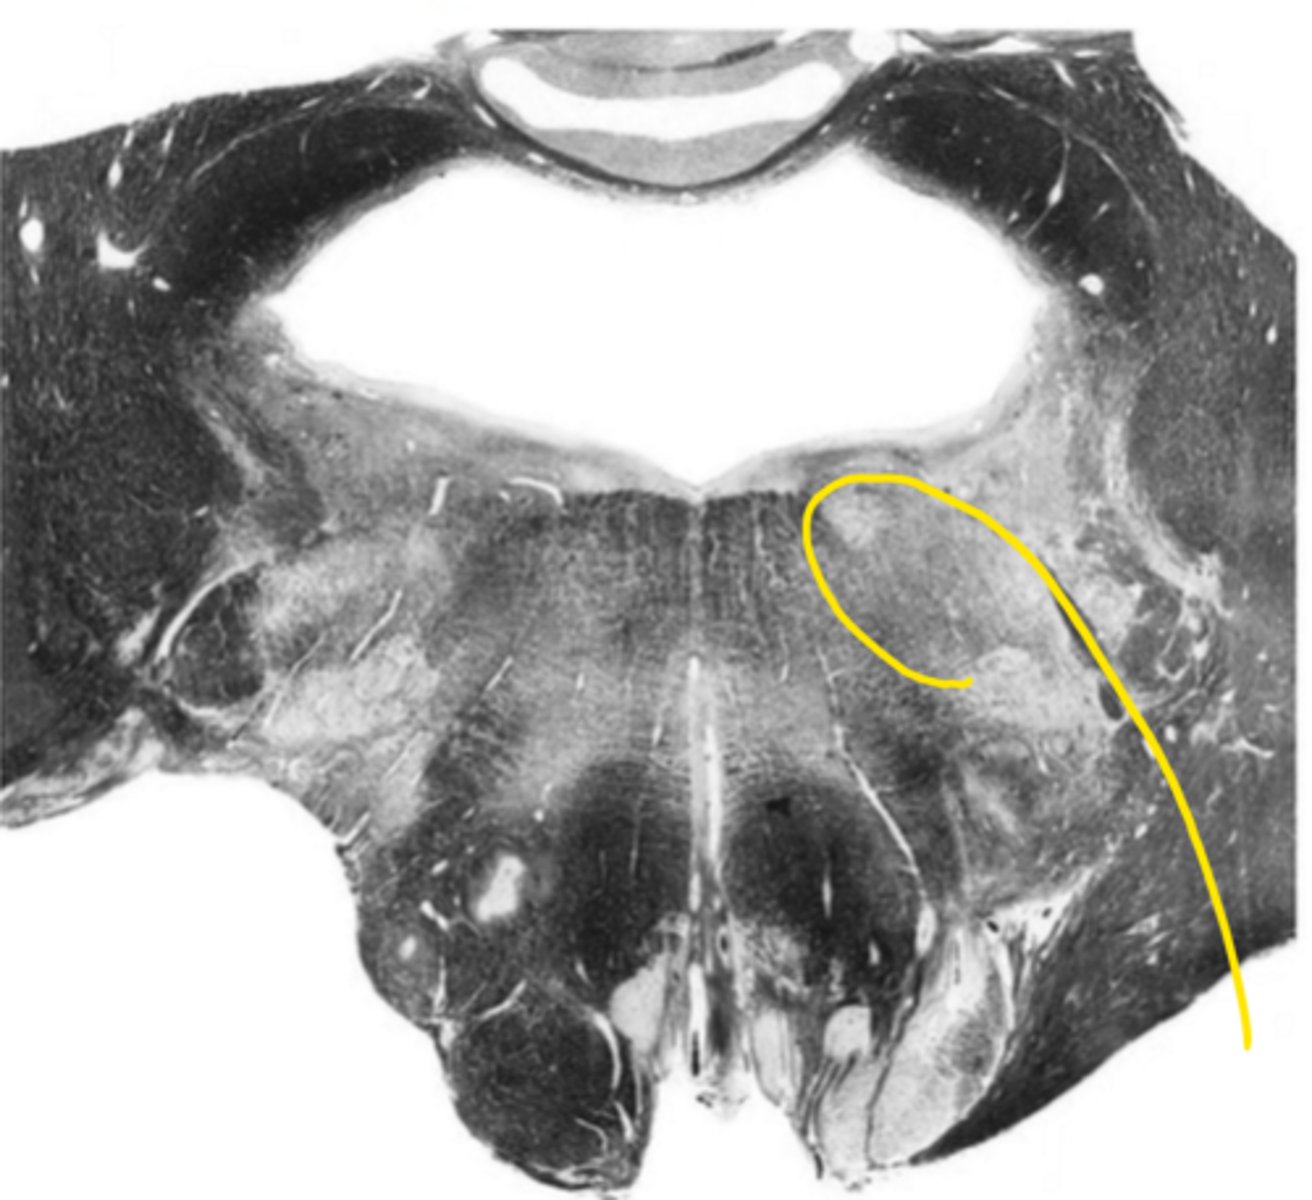

vestibular nucleus

ID the nucleus

foramen of Luschka

ID the space

cochlear nucleus

glossopharyngeal nerve

ID the nerve

fourth ventricle

hypoglossal nucleus

inferior cerebellar peduncles

ID the structure

reticular formation

vagus nerve

principle olivary nucleus

corticospinal fibers

hypoglossal nerve

medial lemniscus

anterior median sulcus